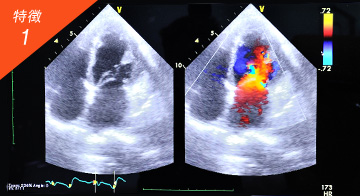

24時間〜48時間前の発作をまるでタイムマシンのように追跡できる最先端の心臓超音波機器「スペックルトラッキング」を用いた診察がございます。

過去に遡れることにより、従来症状がある時点で心電図を撮らないと異常は出なかった問題を解消でき、原因の早期発見が期待できます。

微小血管狭心症の診断に強いのもスペックルトラッキングの特徴です。